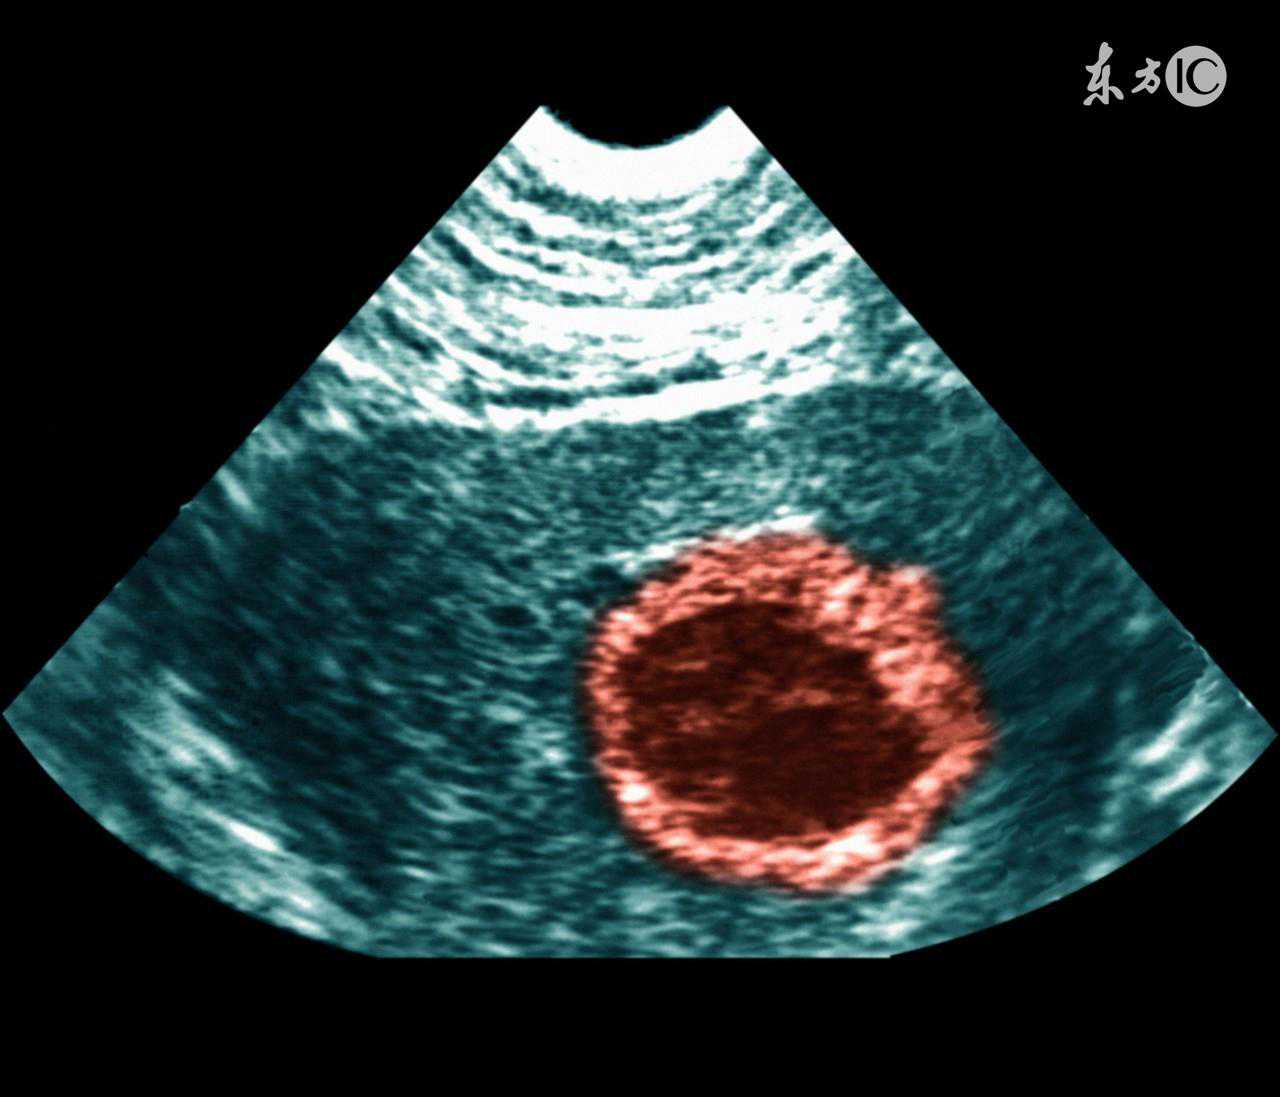

不过转折这在1月份,我那个月没有检测,基础体温高温只有10天,我想完蛋了,现在又黄体不足了,怀孕更难了,赶紧去医院补孕酮,调整中药方子,每个月的紫河车喝的太噁心了,因为我排卵前的那段时间很长要22天,排卵后大概只要13天,雌激素不足。到2月份也是检测了一个月还是没中,右测排卵,我想可能我以前做过阑尾手术,右侧输卵管不通了。2月28号月经来了。3月份,我准备左侧排卵的时候,看下能否怀孕,如果不行就4月份做输卵管造影了,都已经跟医生约好了,哪知3月份月经突然变成了30天了,我以为还是35天,医生给我开了14天的中药,要我吃完去做卵泡检测,月经后几天,我和老公分居,正好他3月14号回家的,我还怪他说回来早了,我还没排卵呢,也没检测,马上又要出差走了,又要错过了。15号晚上,随手测了一张试纸,居然是阳,吓了一跳,怎会排卵了?!还不太相信,当晚没有同房,第二天早上量基础体温的时候居然体温降低了,我知道排卵了,赶紧补了一次。然后就周日了,晚上也没有同房,他要出差了,就没有指望了这个月会中,因为也没有检测卵泡,不知道发育的怎样。哪知过了一周,也就上周,肚子针戳一样的疼,而且是右侧疼,我应该是左侧排卵的,不可能右侧疼啊,也就没往着床那边想,还以为自己又的了什么肝痉挛之类的呢。而且没有什么着床降温和出血,更不会往怀孕上想了。然后周一开始大腿和屁股好酸,像跑了几公里一样,嘴里干巴巴的感觉,我那时候隐隐约约感觉中了,前天早晨测真的有淡淡的印了!一天天加深,昨晚突然白带里有血丝了,正好今天是停经一个月,我以为月经又来了,哭死了,哪知今早基础体温没降,试纸还加深了,赶紧去医院,就是Hcg有点低,要保胎,虽然我现在还没稳定,可能还出血,不过我相信肯定会宫内好孕,平平安安的!